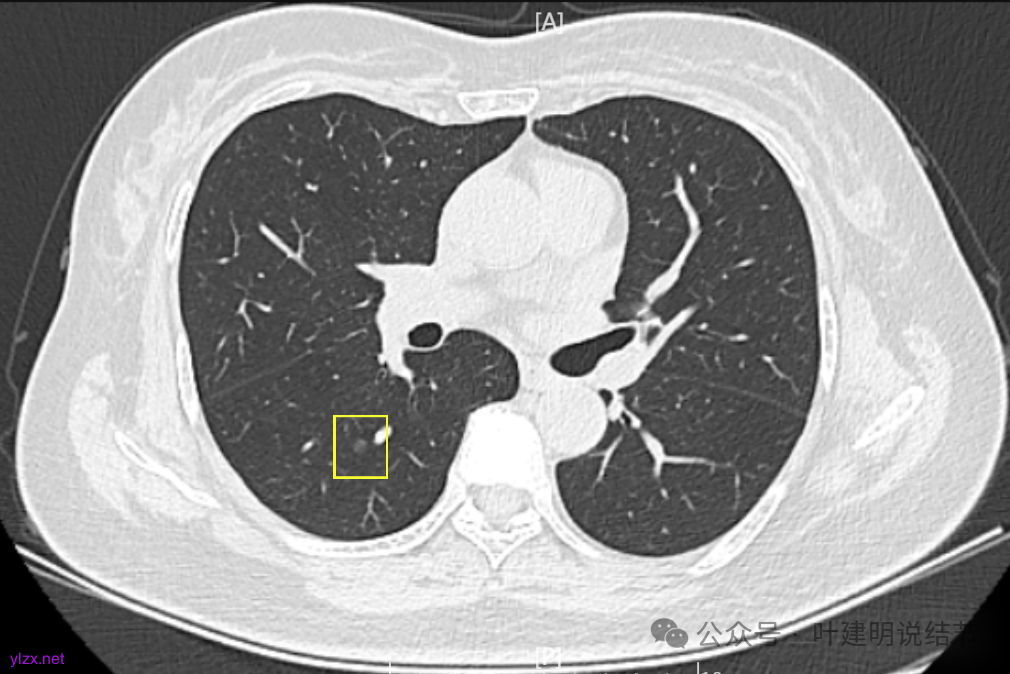

8.2023年1月B医院复查ct,显示最大肺结节0.85*0.73cm,其余变化不大。

9.2023年4月复查ct,显示最大肺结节0.79*0.72。2023年3月短暂去某地疗养一月。

10.2023年11月28日复查CT,显示最大结节0.8*0.7cm。

我们发现其实各病灶与三年前比说不上显著进展。